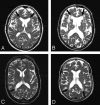

Purpose: Our aim was to assess whether presumed histologic heterogeneity of age-related white matter hyperintensities (WMH) is reflected in quantitative magnetization transfer imaging measures.

Materials and methods: From a group of patients participating in a double-blind placebo-controlled multicenter study on the effect of pravastatin (PROSPER), we selected 56 subjects with WMH. WMH were classified as periventricular WMH (PVWMH) and deep WMH (DWMH). PVWMH were subclassified as irregular or smooth, depending on the aspect of their border. Signal intensity of WMH on T1-weighted images was scored as iso- or hypointense. The mean magnetization transfer ratio (MTR) value of different types of WMH was assessed and compared. As a control group, we selected 19 subjects with no or limited WMH.

Results: Mean (SE) MTR of PVWMH (frontal, 31.2% [0.2%]; occipital, 32.2% [0.2%]) was lower than that of DWMH (33.7% [0.5%]). The mean MTR of frontal PVWMH (31.2% [0.2%]) was lower than that of occipital PVWMH (32.2% [0.2%]). Compared with occipital PVWMH, frontal PVWMH more often had a smooth lining (72% frontal versus 8% occipital) and an area with low signal intensity on T1-weighted images (76% frontal versus 35% occipital). MTR did not differ between smooth (31.1% [0.3%]) and irregular (31.6% [0.5%]) PVWMH.

Conclusion: Age-related WMH are heterogeneous, despite their similar appearance on T2-weighted images. By taking into account heterogeneity of age-related WMH, both in terms of etiology and in terms of severity of tissue destruction, one may obtain better understanding on the causes and consequences of these lesions.